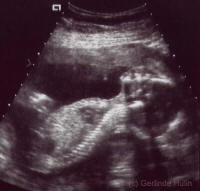

Ultraschall

In unserer hausärztlich strukturierten Praxis bieten wir ihnen eine

umfassende Untersuchung der Bauchorgane wie Leber, Nieren, Gallenwege

usw.

an.

Sonographie,

auch Echographie oder umgangssprachlich Ultraschall genannt, ist die

Anwendung von Ultraschall als bildgebendes Verfahren zur Untersuchung

von organischem Gewebe in der Medizin sowie von technischen Strukturen.

Die Sonographie ist das am häufigsten genutzte bildgebende Verfahren in

der Medizin überhaupt. Ein wesentlicher Vorteil der Sonographie

gegenüber dem in der Medizin ebenfalls häufig verwendeten Röntgen liegt

in der Unschädlichkeit der eingesetzten Schallwellen. Auch sensible

Gewebe wie bei Ungeborenen werden nicht beschädigt, die Untersuchung

verläuft weitgehend schmerzfrei.